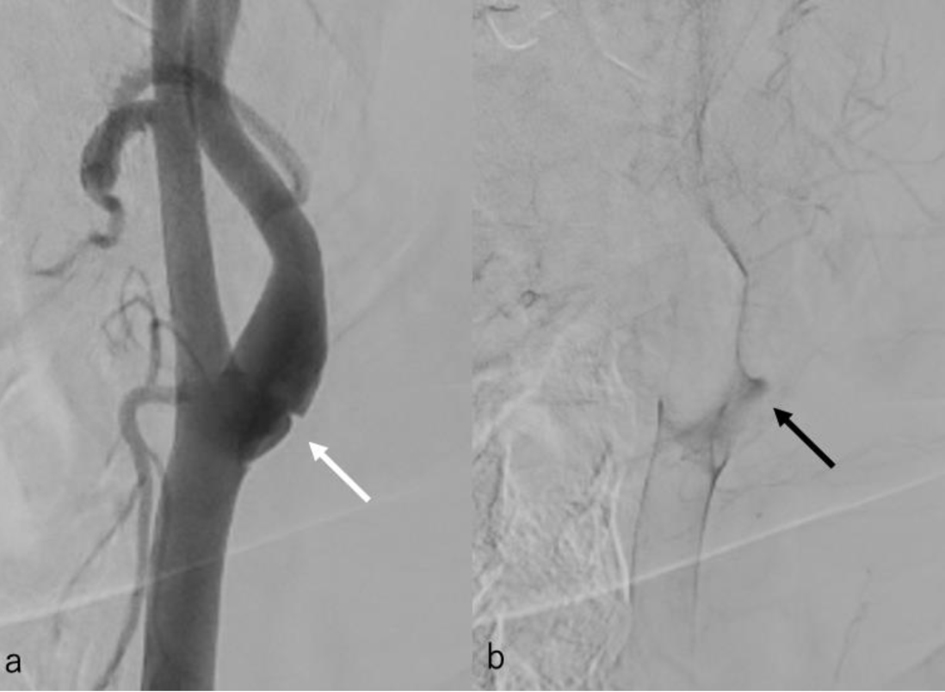

The following day, no apparent hemorrhagic extension was observed. On carotid artery ultrasonography, there was a mobile lesion at the origin of the left ICA (Fig. 2). Further examination with three-dimensional computed tomography angiography (3D-CTA) revealed the presence of irregular contrast in the posterolateral wall of the left cervical ICA origin (Fig. 3a-d). MRI plaque image revealed a structure that was T1 isointense (Fig. 4a) and T2 high intense (Fig. 4b) with the vessel wall, protruding into the lumen (Fig. 4). On the second day, cerebral angiography revealed a shelf-like structure on the posterior wall of the left ICA origin (Fig. 5a), and the left MCA was recanalized. Cerebral angiography revealed pooling of blood flow on the rostral side of the lesion (Fig. 5b).

Figure 3. Three-dimensional computed tomography angiography revealed the presence of irregular contrast in the posterolateral wall of the left cervical internal carotid artery origin. (a) Sagittal image (white arrow); (b-d) axial images (black arrow).